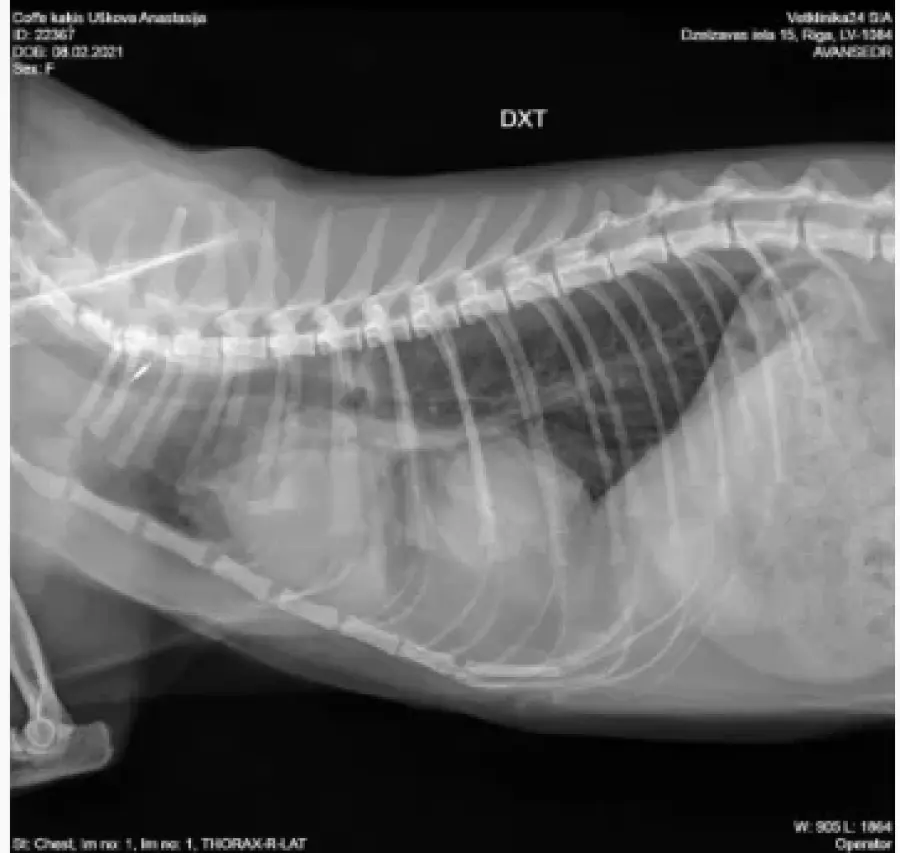

Хочу поделится своей историей покупки взрослой кошечки породы Девон рекс у заводчицы Zainaba Balabaja из питомника «Bambielf Mystery», которая в итоге оказалась больная, с врожденной деформацией диофрагмы, сросшимися органами, сжатым правым легким и еще кучей других проблем. Питомник зарегистрирован на имя её дочери Ирины Скобовы в Саласпилсе, по факту заводчица проживает и разводит котят в плявниеках. Если вкратце, весной 16го марта я приобрела у заводчицы кошечку породы Девон Рекс 4х лет, которая использовалась для разведения котят. Я и мой молодой человек созвонились с заводчицей и приехали к ней в скором времени посмотреть кошечку. В квартиру она нас не пустила, аргументируя тем что она и её муж возрастные, переболели ковидом и никого не пускают, а я наивная во все это поверила, так как это был мой первый опыт с заводчиками. Кошечку вывели на лестничную клетку в переноске, визуально она выглядела здоровой. Мы договорились об оплате наличными в размере 450 евро, о перерегистрации паспорта на меня и стерилизации через месяц в рекомендованной ей клинике, так как кошке недавно делали прививку. Договор и родословную она мне не выдала. Когда я забирала паспорт, она сказала что родословная нужна в том случае если я собираюсь водить кошку на выставки, и я решила не платить за перерегистрацию родословной на меня, так как не планировала кошку ни разводить, ни участвовать в выставках. Когда кошка начала жить у меня, спустя некоторое время у нее начали слезится глаза, заводчица уверяла что это из-за прививки. После я начала замечать что кошка часто чешется в районе подбородка и ушей, глаза все время слезились и она начала кашлять. После стерилизации кашель ухудшился, на что в клинике мне ответили что скорее всего кошка аллергик, сделали ей стероидный укол после чего симптомы прекратились на несколько недель, а потом все началось заново. На мои просьбы сделать анализы и рентген был отказ. После по совету ветов я водила кошку к вет дерматологу Евгении Кондратьевой на две консультации, были выписаны медикаменты от паразитов и курс чистки ушей, но кашель и частые чесания ушей и подбородка не прекратились. После был выписан бронхиальный ингалятор, это тоже не помогло. На мои просьбы о том, что я хотела бы сделать сразу рентген и сдать анализы был отказ, мол, надо наблюдать. В итоге в один вечер у кошки был очередной приступ кашля, который длился не минуту как обычно, а около 5-10 минут с перерывами. Я и парень повезли её в клинику Vet24, где сразу сделали рентген, взяли анализы и проверили на клещей. Какого было наше удивление когда вет принесла рентген с непонятным большим образованием давящим на органы, сказала что это не похоже на рак, но нужно делать КТ и проверить сердце. В итоге через пару дней ей сделали КТ, через месяц проверили сердце. Есть еще подозрение на проблемы с печенью, анализы на мочу показали наличие кристаллов песка. В итоге у кошки диагностировали PPDH, вкратце у кошки пока она была в эмбриональном развитии неправильно сформировалась диафрагма, образовалось отверстие и через него вышла печень и срослась с сердечной сумочкой. Органы давят на левое легкое. Правое сжатое. Сердце при этом, слава богу, пока что в порядке. Отдали мы на ветов уже больше 1000 евро, успели поменять куча кормов чтобы уменьшить симптомы аллергии и чтобы не было нагрузки на печень, переодически используем стероидный ингалятор, кошке предстоит пожизненное наблюдение у ветов, ежегодные обследования. После консультации с хирургом был сделан вывод что операцию делать смысла нет, так как с большей вероятности кошка просто умрет от потери крови. Если еще учитывать, что кошка давала потомство минимум раз в год за свои 4 года, котята давили на и так деформированные органы, а кашель заводчица просто не могла не замечать, у меня складывается подозрение что заводчица за всю жизнь кошки даже нормально ее ни разу не обследовала у вета, хотя животное ей создавало доход. Так же я нашла отзыв на sudzibas.lv за 2023 год, где мужчина приобрел двух котят у этой же заводчицы, которые оказались с клещами и хламидиозом. Жалобу я, конечно же, увидела слишком поздно. Та же схема, не пускает в квартиру посмотреть котят под предлогом ковида и уверяет что котята здоровые, а слезящиеся глазки после прививки. Сумма на ветов и обследования за пол года уже привысила 1000 евро и бог с этими деньгами на лечение, меня больше всего злит обман и абсолютное потребительское отношение к животным, которые создают тебе доход. С заводчицей после получения вет паспорта я в дальнейшем не контактировала, так как не вижу смысла выяснять отношения с человеком, который меня намеренно обманул и продал больное животное. Считаю что здесь нужно подключать соответсвующие инстанции. Скрины заключений, КТ, рентгенов прикреплю к посту. Так же сохранились скриншоты переписок с заводчицей, объявление о продаже кошки, большая часть выписок и переписок с ветами.

Прикладываю копию рентгена, результата КТ, объявление о продаже кошки, профиль заводчицы и название питомника в списке клуба Mooncat сюда в комментарии